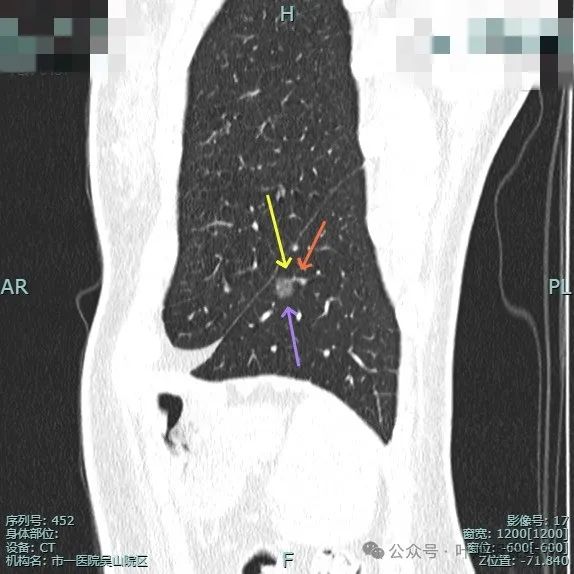

左肺淡磨玻璃结节,轮廓与边界较为清楚。

有微小血管走向病灶,而且病灶表面欠平滑。

病灶离叶间裂较近,几乎贴着,叶间胸膜略有牵拉向病灶侧,但力量小。可见有一细小血管走向病灶。